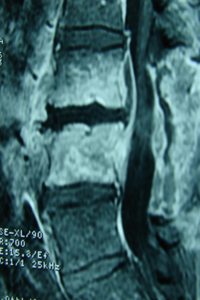

Ο ακτινολογικός έλεγχος προ της εισαγωγής του έδειξε :

Εικόνα 1 (α,β)

Παρατηρούνται τυπικές εκφυλιστικές βλάβες των οσφυϊκών σπονδύλων, συμβατές με την ηλικία του ασθενούς. Ο ακτινολογικός έλεγχος δια απλών ακτινογραφιών δεν έδωσε ιδιαίτερα διαγνωστικές πληροφορίες.